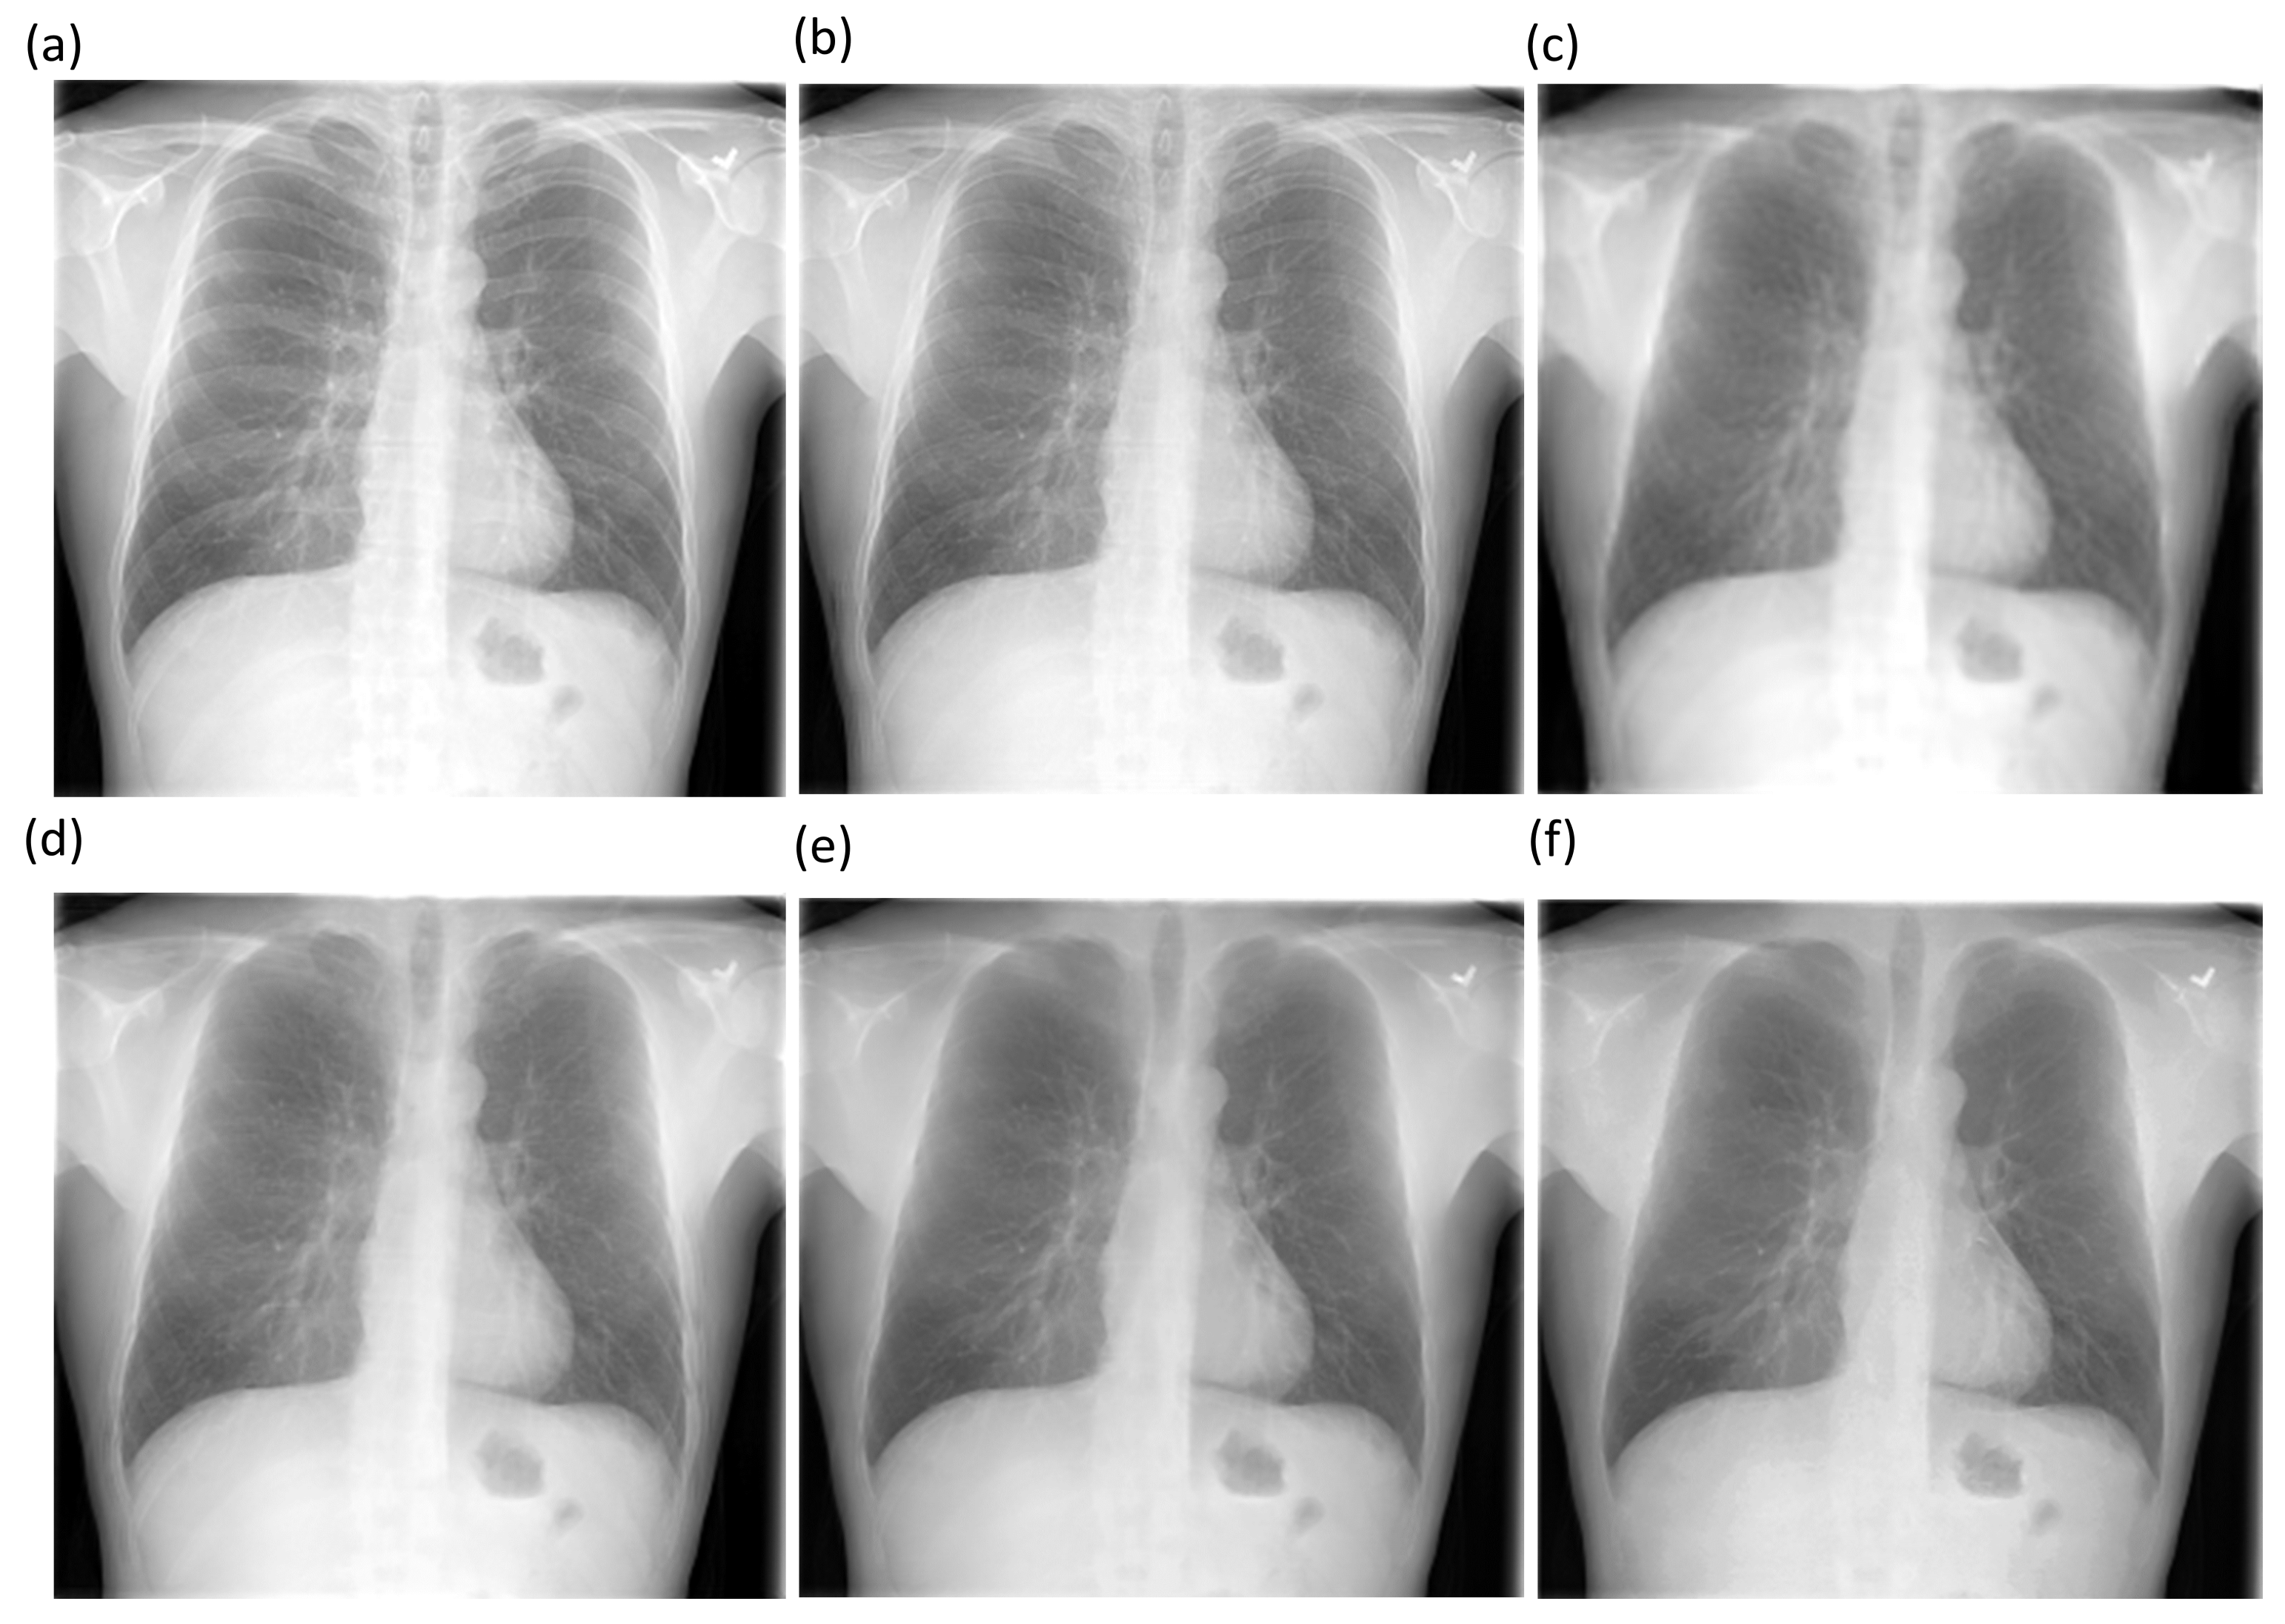

It is observed that the 95% CI for the MS–SSIM metric achieved by the ResNet–BS model demonstrates a tighter error margin and hence higher precision, compared to the other models. The ResNet–BS model demonstrated the least values for the combined loss, MAE, and MS–SSIMloss and superior values for PSNR, SSIM, and MS–SSIM. The ResNet–BS model statistically significantly outperformed the AE–BS model (p < 0.05) and the ConvNet–BS and RL–BS models for the PSNR metric (p < 0.05). For other metrics, the ResNet–BS model demonstrated superior performance than the CNN–BS, and RL–BS models. Figure 5 shows the final bone suppression images along with the original unsuppressed CXR from a normal CXR in the NIH–CC DES test set. All approaches appear to show substantial suppression of the bony structures in the apical regions. For differentiation among them, quantitative indices are needed. A quantitative comparison of the bone-suppressed CXR images in Figure 5 is provided by histogram similarity comparisons in Figure 6 and Table 3 that follow. Based on the comparison findings, the ResNet–BS model was used in subsequent analyses.

Figure 5. Bone-suppressed CXR images predicted by the proposed models using a CXR sample from the cross-institutional NIH–CC DES test set. (a) Original CXR; (b) AE–BS model; (c) ConvNet–BS model; (d) RL–BS model; (e) ResNet–BS model; and (f) Ground truth.